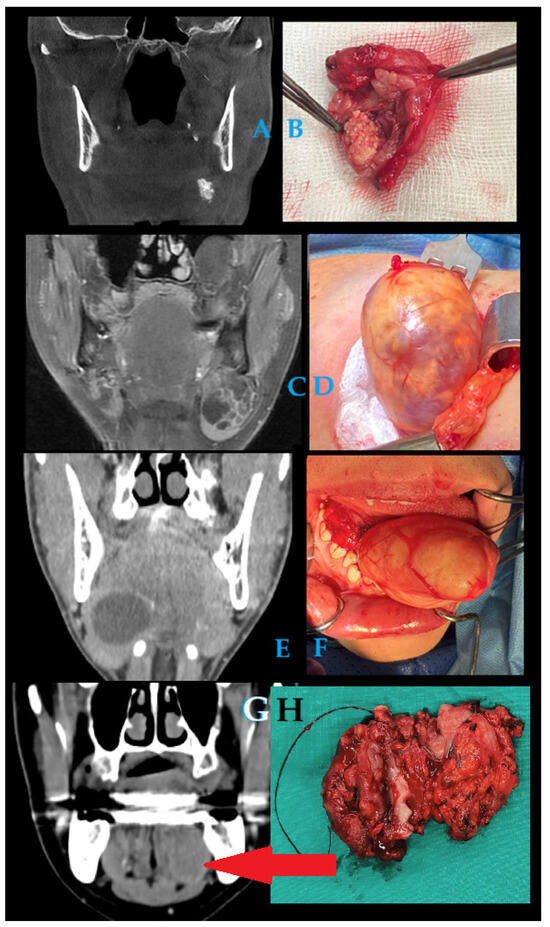

It is with great pleasure that I invite you to submit articles for the “Interesting images” Special Collection. Since we introduced Interesting Images as an article type in Diagnostics, it has served as a valuable resource for the imaging community. Many have relayed that they use these image-based case reports when encountering challenging cases or images of diseases rarely seen. Further, pitfalls are covered by this type of article and may be helpful both for experienced and less experienced image readers in making a correct evaluation.

The interesting Images together serve as a live imaging atlas covering PET, CT, MRI, and other imaging modalities. Therefore, the more cases we publish, the more likely it is that image interpreters with a difficult case can be supported by previously published cases. Although focus until now has largely been on clinical cases, it should be noted that nonclinical cases are also welcome, e.g., from preclinical in vivo imaging, including optical imaging as well as histology images from pathology.